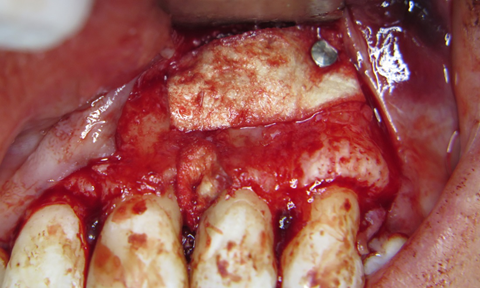

За допомогою інструментів CL 84, 141-004-31W Oval Spoon Excavator (Hu-Friedy) та пародонтальних кюрет Langer (Hu-Friedy) видалено грануляційну тканину з пародонтальної кишені та периапікальної ділянки. Оскільки, ендодонтичне лікування проведено в повному обсязі. Кореневий канал запломбовано до апікальної конструкції, прийнято рішення про відмову від ретроградного пломбування. Дефект заповнено кістковим матеріалом ксеногенного походження BIO GEN cancellous size 2/3 mm, 2.0 (Bioteсk), використана бар’єрна мембрана BIOCOLLAGEN (Bioteсk), пародонтальний дефект заповнено BIO GEN mix (Bioteсk). (фото 6, 7)